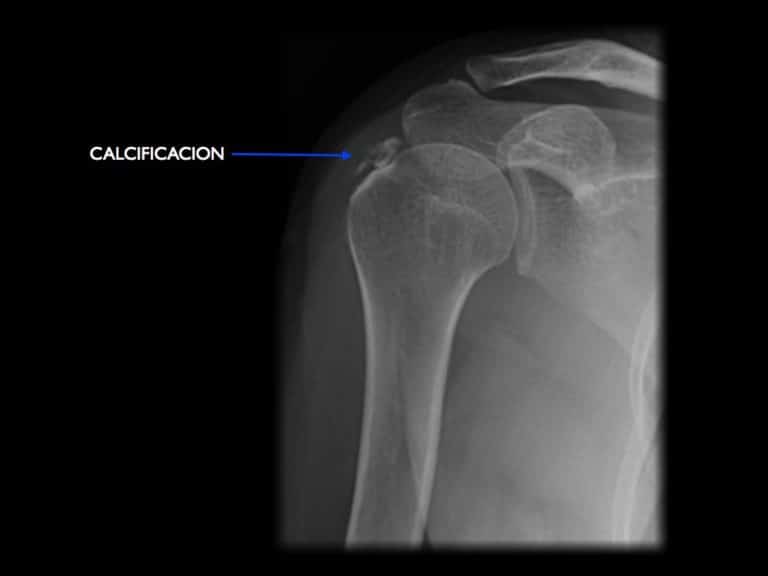

Calcificación En El Hombro Enfermedad Profesional, Calcificaciones. Cuáles son los síntomas y el tratamiento de las complicaciones, 7.07 MB, 05:09, 235,098, CanalSalud, 2016-01-26T01:52:43.000000Z, 3, Tendinitis Calcificada Hombro | SportClinic Guatemala, sportclinic.com.gt, 960 x 960, jpeg, WebUna calcificación de hombro es una tendinitis calcificante de hombro; consiste en un cúmulo en forma de depósito de pirofosfato cálcico intratendinoso. La calcificación de hombro es una causa frecuente de hombro doloroso , es de causa. Webcomo enfermedad profesional Enfermedades provocadas por posturas forzadas y movimientos repetitivos en el trabajo; enfermedades por fatiga e inflamación de las. WebSi crees que puedes sufrir calcificaciones en el hombro, es importante que visites a tu médico para que pueda analizar tu caso y recomendarte un tratamiento., 20, calcificacion-en-el-hombro-enfermedad-profesional, Novedades y Muebles WebUna calcificación de hombro es una tendinitis calcificante de hombro; consiste en un cúmulo en forma de depósito de pirofosfato cálcico intratendinoso. La calcificación de hombro es una causa frecuente de hombro doloroso , es de causa. Webcomo enfermedad profesional Enfermedades provocadas por posturas forzadas y movimientos repetitivos en el trabajo; enfermedades por fatiga e inflamación de las. WebSi crees que puedes sufrir calcificaciones en el hombro, es importante que visites a tu médico para que pueda analizar tu caso y recomendarte un tratamiento.

WebLa tendinitis calcificante del hombro es el proceso originado por la formación de depósitos cálcicos en los tendones del hombro que forman el llamado “manguito rotador” y que. WebComo patologías de hombro derivadas de Enfermedad Profesional, se encuentran tanto la patología degenerativa del manguito rotador, la más importante sin lugar a dudas,. WebLa calcificación en el hombro se conoce también como tendinitis calcificante del hombro. Como su nombre lo indica, ataca a esta articulación grande que regula el. WebTambién llamada tendinitis calcificante, las calcificaciones en el hombro ocurren cuando aparecen depósitos de calcio sobre los tendones del hombro. El calcio provoca la. WebIncapacidad Permanente por patologías de hombro. El primer paso para evaluar una posible Incapacidad Permanente por patologías de hombro es clasificar la gravedad de. WebLa tendinitis calcificada del hombro se produce cuando se forman depósitos de calcio en los tendones del hombro. Los tejidos que rodean el depósito pueden.

WebUna calcificación en el hombro es una condición en la que se forma un trozo de calcio en el tejido blando del hombro. Esto puede causar dolor e. WebLa tendinitis calcificante de hombro puede clasificarse en tres etapas: La primera es la etapa precalficicante, en la cual se producen cambios celulares en el lugar donde se está. WebLa tendinitis calcificada, como su nombre indica, es el depósito de calcio en el manguito de los rotadores de los hombros. El manguito de los rotadores es un.